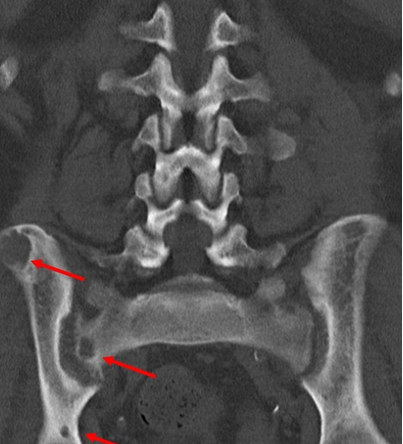

Рис. 6: Магнитно-резонансная томография (МРТ) – множественные гиподенсные очаги костей таза, имеющие кистозный характер